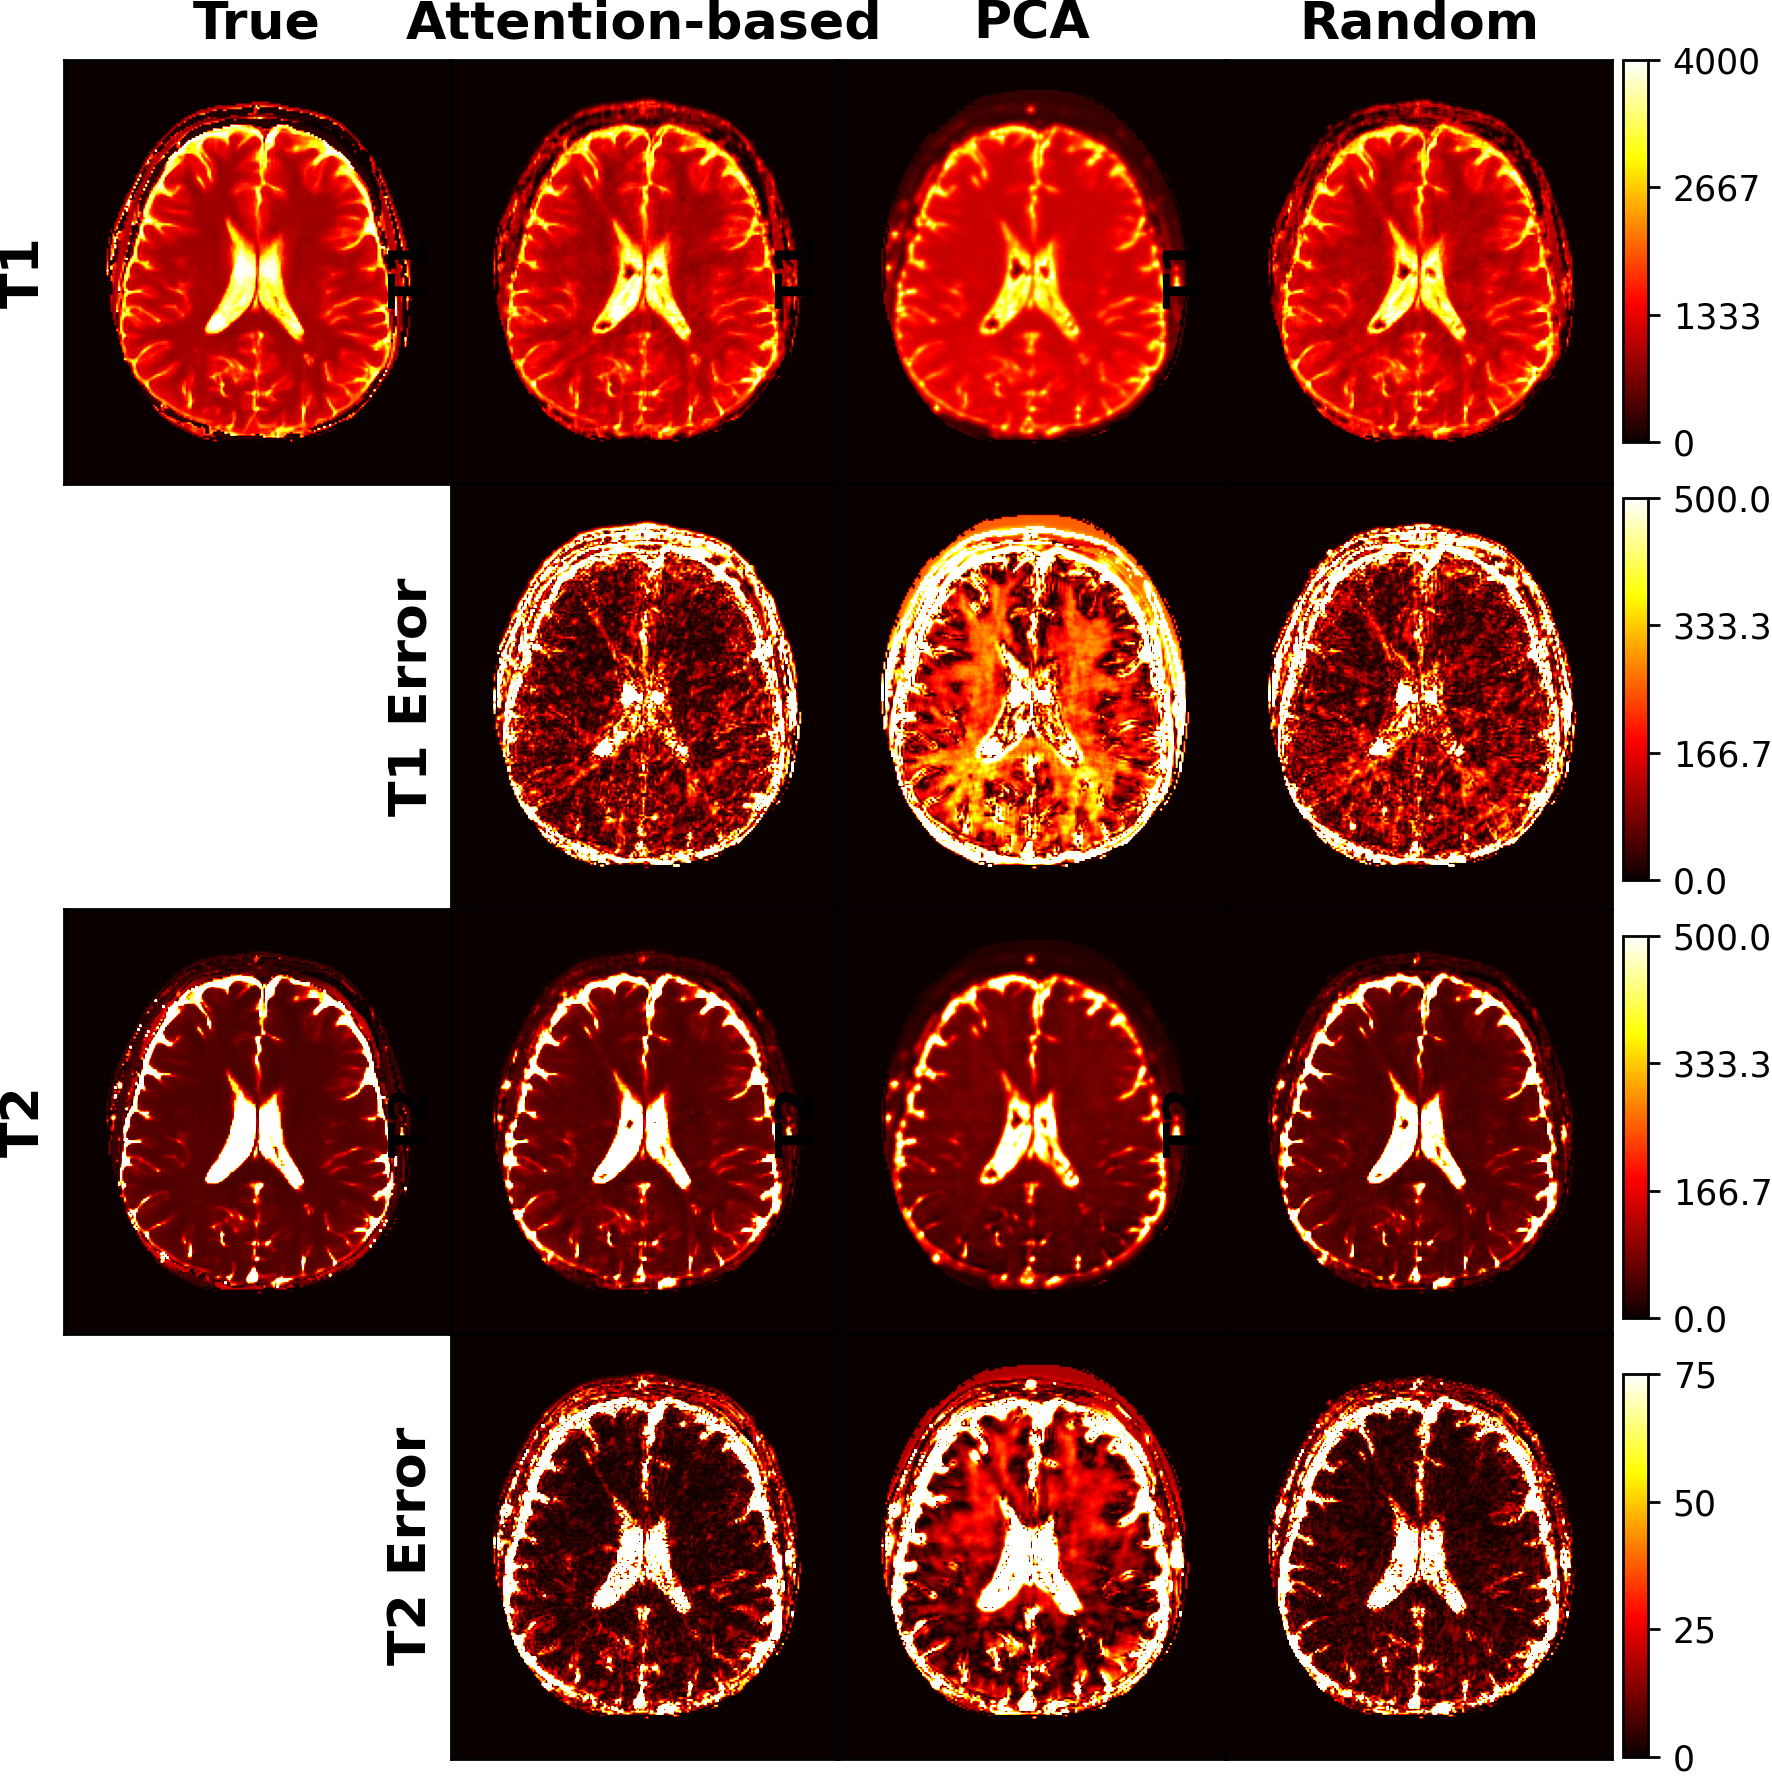

Refer to caption

Figure 7: Channel selection methods are compared with true tissue parameters, T1 and T2 respectively, when channel size is reduced from 2000 to 40. The rows marked as T1 and T2 (1st and 3rd rows, respectively), show the reconstructed tissue parameters by the models. T1 error and T2 error images (2nd and 4th rows, respectively) show the differences between the reconstructed and true tissue parameters.

The channels are analyzed to investigate the important channels for reconstruction and to eliminate redundant ones. Through the determination of the most important channels, n𝑛n channels are selected to enhance tissue parameter reconstruction. We proposed a new channel selection method: attentionbasedselection𝑎𝑡𝑡𝑒𝑛𝑡𝑖𝑜𝑛𝑏𝑎𝑠𝑒𝑑𝑠𝑒𝑙𝑒𝑐𝑡𝑖𝑜𝑛attention-based~{}selection. To evaluate the performance of the proposed channel selection method empirically, we experimented with two more channel selection schemes, PCA-based and random, and carried out a performance comparison with our proposed method. Table IV shows MAE errors in percentage (Equation 3), between the ground truth and reconstructed image for n𝑛n number of channels selected by the methods: Attention-based, PCA, and Random. Following the channel selection, the proposed model CONV-ICA is used for training. For performance evaluation, 3-fold cross validation is carried out by using the mean absolute error in percentage as a metric. Quantitative results presented in Table IV show that attention-based channel reduction results in a decrease in the reconstruction error while PCA-based and random selection schemes cause to increase the reconstruction error. The important advantage of attention-based channel selection is reducing the need of resources and run time for algorithms.

TABLE IV: Comparison of cross validated mean absolute error (MAE) errors in percentage for each channel selection method, attention-based selection, reduction by PCA and random channel selection when n𝑛n number of channels are selected for both T1 and T2 values.

Method / n𝑛n T1 - MAE(%) T2 - MAE(%)

Attention / 100 2.07 0.79

PCA / 100 6.22 1.48

Random / 100 2.26 0.84

Attention / 200 1.88 0.68

PCA / 200 4.49 1.71

Random / 200 2.08 0.69

Attention / 300 1.93 0.77

PCA / 300 4.85 1.65

Random / 300 2.08 0.78